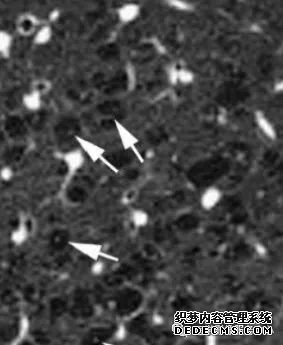

肺内淋巴结的CT表现特点及与病理对照